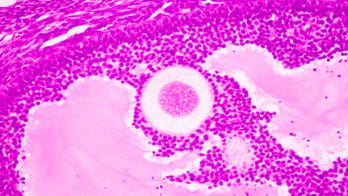

Infertility December 12, 2016 Can chemotherapy drug ‘turn back the clock’ in women’s ovaries? It's generally thought that women are born with a finite number of egg cells, and cannot grow new ones.